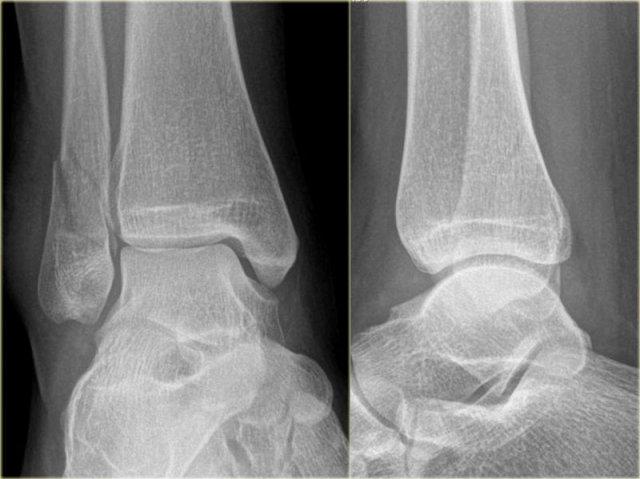

Weber B in detail

Stage 1-2

Weber B là loại gãy xương mắt cá chân phổ biến nhất, chiếm khoảng 60%.

Theo Lauge-Hansen, gãy xương này là kết quả của lực xoay ngoài tác động lên bàn chân ở tư thế sấp.

Giai đoạn 1 thường không thể nhìn thấy trên phim X-quang.

Điều chúng ta thường thấy là gãy xương chéo giai đoạn 2 qua khớp chày mác và chúng ta phải giả định rằng cũng có đứt dây chằng chày mác trước, tức là giai đoạn 1.

Theo Lauge Hansen, tổn thương đầu tiên xảy ra ở phía ngoài, nơi đang chịu lực căng tối đa.

Ở giai đoạn 2, xương sên tiếp tục xoay ngoài và do bàn chân đang ở tư thế sấp, mắt cá ngoài bị giữ chặt tại chỗ bởi các dây chằng bên ngoài.

Mắt cá ngoài không thể di chuyển ra ngoài mà không bị gãy.

Kết quả là sự xoay tiếp tục của xương sên sẽ gây gãy xương mác theo kiểu chéo hoặc xoắn ốc do mắt cá ngoài bị đẩy bật ra từ phía trước trong ra phía sau ngoài.

Các hình ảnh cho thấy gãy xương Weber B.

Đường gãy chéo là đặc trưng điển hình của Weber B và là kết quả của sự xoay ngoài của xương sên đẩy vào mắt cá ngoài cố định.

Gãy xương mắt cá thường bắt đầu ở phía trong tại mức vòm xương sên, nhưng cũng có thể bắt đầu cao hơn mức này vài centimet.

Hình ảnh X-quang cho thấy một gãy xương Weber B điển hình.

Hãy quan sát kỹ hình ảnh trước rồi tiếp tục đọc.

Bạn có nhận ra đây là giai đoạn nào không?

Đây là tổn thương Weber B giai đoạn 4.

Lưu ý rằng cả 4 giai đoạn đều có thể nhìn thấy:

- Đứt dây chằng chày mác trước – biểu hiện bằng sự giãn rộng khoảng cách giữa đầu xa xương chày và xương mác (khoảng sáng bên ngoài).

- Gãy xương mác chéo ở mức khớp chày mác – tức là gãy kiểu Weber B.

- Gãy xương Tertius – thấy trên phim thẳng (mũi tên đỏ) và trên phim nghiêng (mũi tên vàng).

- Rupture của dây chằng bên trong – được thấy như sự mở rộng của khoảng cách giữa mắt cá chân trong và xương sên (khoảng sáng trong)